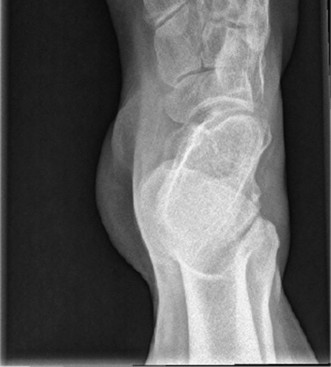

A 16-year-old male presents noting frequent sprains to his right ankle. He notes that he rolls his right ankle several times a day, and also describes pain along the lateral border of his foot. His left ankle is similarly symptomatic, but not quite as severe. Radiographs are obtained (Figs. 5–3 and 5–4).

Figure 5–3 Lateral weight-bearing radiograph of the foot.